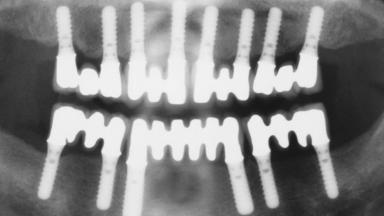

Immediate Loading of Eight Implants in the Maxilla and Six Implants in the Mandible and Final Restoration with Three-Unit and Four-Unit FDPs

German Gallucci, Jean-Pierre H Bernard, Urs C Belser

Extensive scientific evidence has confirmed that immediately loaded implants with fixed full-arch provisional restorations can osseointegrate with success rates similar to conventionally or delayed loaded implants. A number of immediate-provisionalization techniques for edentulous jaws have been described. Some protocols differ when it comes to prefabricated provisional templates versus complete denture conversion; intrasurgical impressions versus direct relining; and cemented versus screw-retained provisional restorations. In this context, complete-denture conversion has been proposed for either intrasurgical impressions or direct relining. Another possibility is the utilization of a prefabricated provisional to be adapted either in the mouth (by direct relining) or in the laboratory (on a working model obtained from an intrasurgical impression).